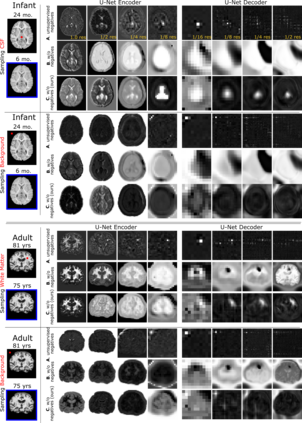

Recent self-supervised advances in medical computer vision exploit global and local anatomical self-similarity for pretraining prior to downstream tasks such as segmentation. However, current methods assume i.i.d. image acquisition, which is invalid in clinical study designs where follow-up longitudinal scans track subject-specific temporal changes. Further, existing self-supervised methods for medically-relevant image-to-image architectures exploit only spatial or temporal self-similarity and only do so via a loss applied at a single image-scale, with naive multi-scale spatiotemporal extensions collapsing to degenerate solutions. To these ends, this paper makes two contributions: (1) It presents a local and multi-scale spatiotemporal representation learning method for image-to-image architectures trained on longitudinal images. It exploits the spatiotemporal self-similarity of learned multi-scale intra-subject features for pretraining and develops several feature-wise regularizations that avoid collapsed identity representations; (2) During finetuning, it proposes a surprisingly simple self-supervised segmentation consistency regularization to exploit intra-subject correlation. Benchmarked in the one-shot segmentation setting, the proposed framework outperforms both well-tuned randomly-initialized baselines and current self-supervised techniques designed for both i.i.d. and longitudinal datasets. These improvements are demonstrated across both longitudinal neurodegenerative adult MRI and developing infant brain MRI and yield both higher performance and longitudinal consistency.